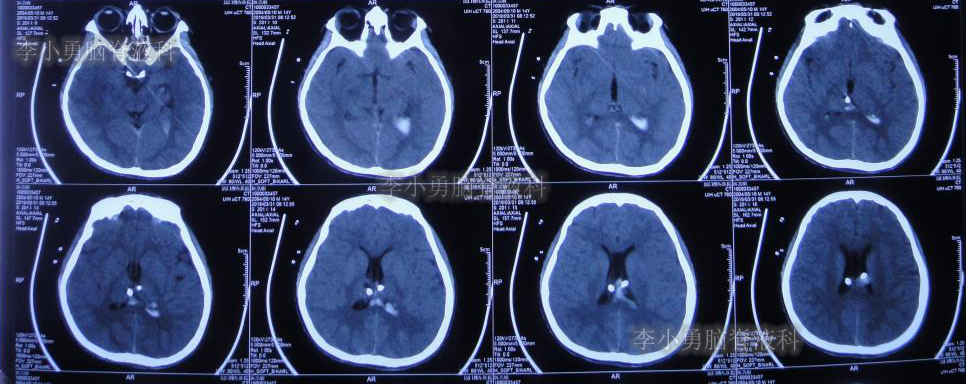

拔管后患者头痛逐渐加重,记忆力逐渐减退。于拔管后11天即2019年6月24日复查头颅CT(图-18):左侧颞角积水加重。

图-18:2019年6月24日头颅CT:左侧颞角扩大加重

次日即2019年6月25日,进行了左侧颞角外引流术;术后次日复查头颅CT(图-19):左颞角引流管位置良好。

图-19:2019年6月26日头颅CT:左侧颞角引流术后

左侧颞角引流术后20天即2019年7月17日,复查头颅CT(图-21):左侧颞角积水消失,水肿消退;患者记忆力也逐渐好转。

图-21:2019年7月17日头颅CT:左侧颞角积水消失,水肿消退

左侧颞角引流术后33天即2019年8月1日,给予试夹闭右侧脑室外引流管,闭管前复查头颅CT(图-22)。

图-22:2019年8月1日夹闭前复查头颅CT

闭管40天后即2019年9月9日复查头颅CT(图-23):脑室仍无扩大。给予拔除右侧脑室外引流管并行左侧颞角-腹腔分流术。

图-23:2019年9月9日头颅CT:拔除右侧脑室外引流管后复查

2019年9月19日(李小勇脑脊液科治4个半月)出院,出院时:意识清楚,能自己走路基本正常,能自己吃饭,日常生活自理,但遗留动脉瘤切除术后记忆力差(图-24)。

出院后2个月即2019年12月9日,复查头颅CT示脑室系统较出院时无明显变化(图-25);但患者记忆力仍差。

图-25:2019年12月9日头颅CT

出院后9个月即2020年7月6日,再次复查头颅CT(图-26):未见异常。家属叙述:肢体活动正常,记忆力较前有些改善但较同龄人仍差,已重返校园(图-27)。

图-26:2020年7月6日头颅CT:未见异常